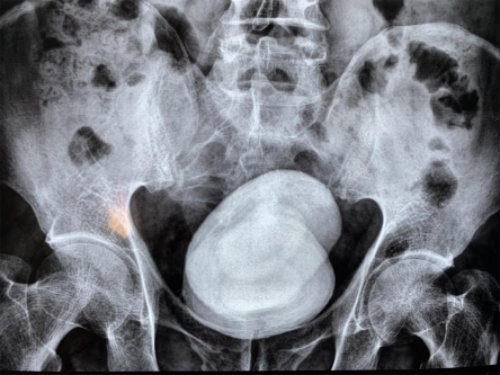

經(jīng)查,鄭先生的膀胱被兩顆直徑長(zhǎng)達(dá)七八公分的結(jié)石充滿,從X光片上看,這對(duì)超大號(hào)結(jié)石就像一對(duì)“雙胞胎”,霸占著他的膀胱。因結(jié)石巨大,醫(yī)生只能采用膀胱切開(kāi)取石的方法將石頭取出。當(dāng)醫(yī)生把兩個(gè)拳頭大的結(jié)石拿給他看時(shí),他對(duì)自己久拖不治的行為懊悔不已。